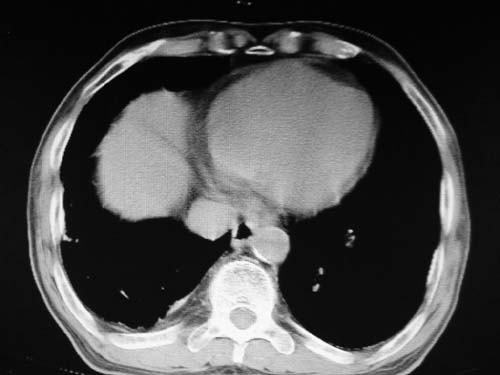

左下肺静脉扩张,原因?建议cta

左肺动脉异常增粗,建议增强。

肺动脉瘤。建议先行ct增强扫描

左肺动脉异常增粗,考虑肺动脉狭窄可能。

1)考虑左肺动脉瘤可能性大,建议增强。2)右肺上叶继发性肺结核。3)右侧胸膜增厚、钙化,左侧胸膜反应。

肺动脉高压,左肺动脉瘤样扩张。